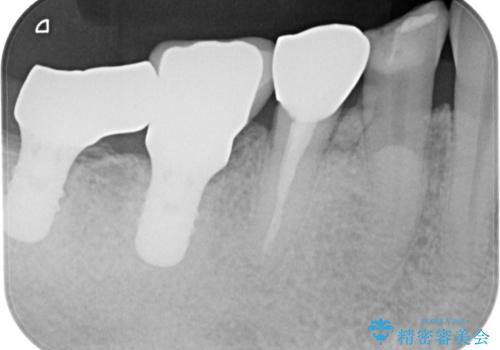

再度詰め物での処置を行うと引き続き欠けるリスクが高いため、高強度のフルジルコニアクラウンにて補綴治療を行うこととしました。

フルジルコニアクラウンは高強度であるため、クラウンの破損リスクは低減されましたが、失活歯(神経を取り除いた)では歯根破折リスクが高いとされており、抜歯の可能性が高まるため適用されません。